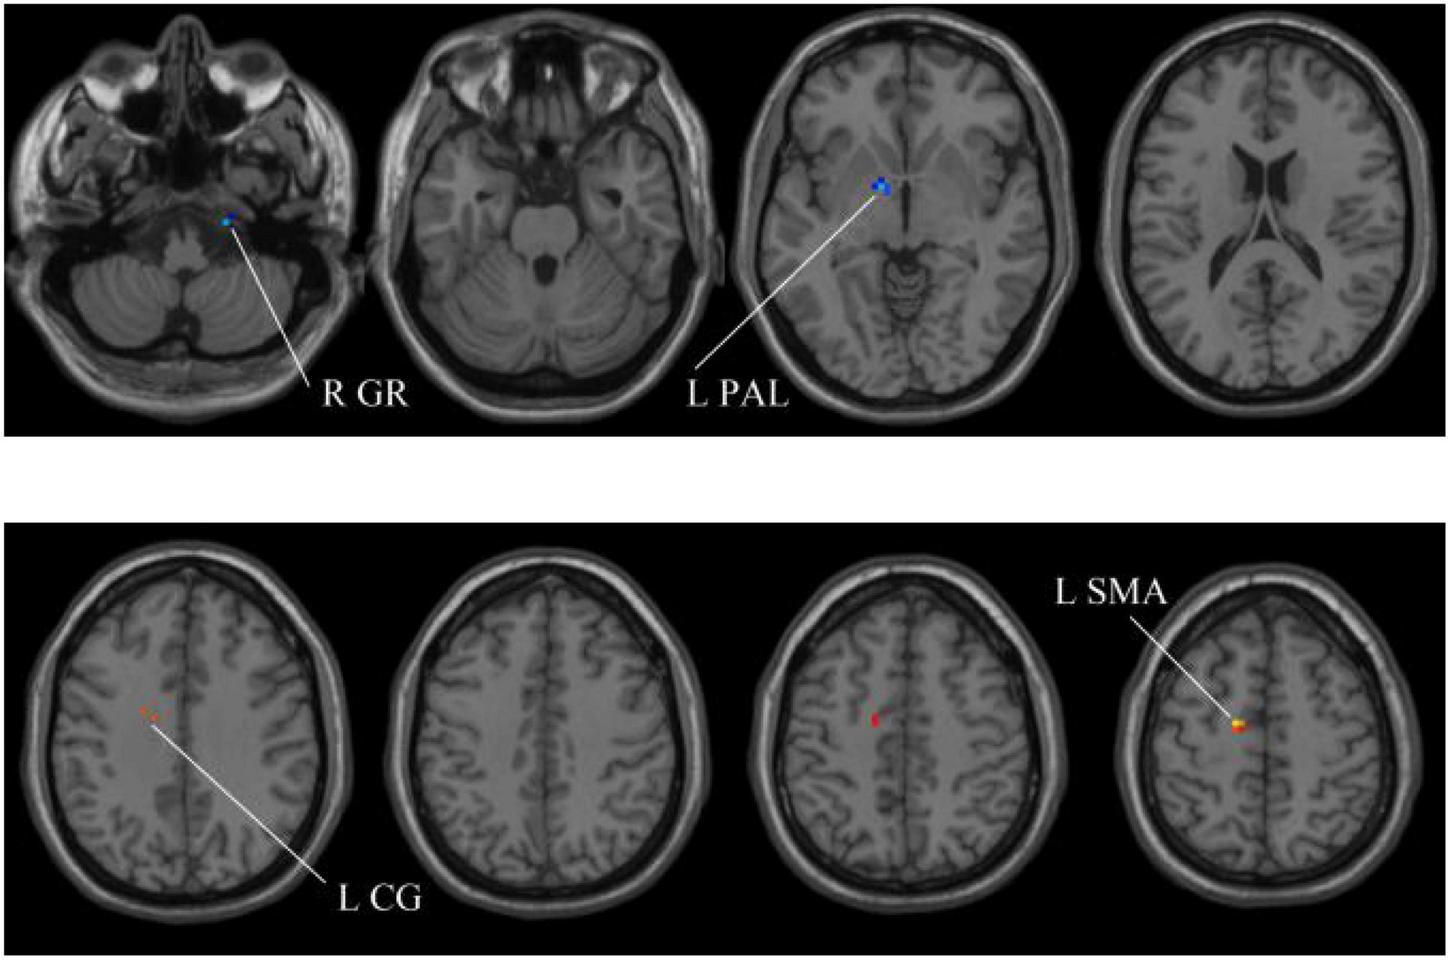

In our experiments, the MGS-WBC model is adopted in two whole-brain structures, including ReHo and ALFF, to reduce the data redundancy and extract multiscale features. For the whole-brain structure calculated by ReHo, as shown in Table 1 and Figures 4, 5, we obtain 10 obvious regions of the brain using MGS-WBC model, including the right gyrus rectus (GR), left pallidum (PAL), left cingulate gyrus (CG), left supplementary motor area (SMA), left inferior cerebellum (IC), right IC, left middle temporal gyrus (MTG), left middle frontal gyrus (MFG), right MFG, and left middle occipital gyrus (MOG), while only six obvious brain regions, namely, left IC, right IC, left MTG, left MFG, right MFG, and left MOG, are found using a single significant threshold (two-sample t-test, p < 0.001). Significantly, each significant region is composed of the activated voxels in the brain. Then, the features extracted from 10 significant regions and six significant regions are separately employed as the input of classifiers, including NB, LDA, LR, and SVM, to evaluate the aMCI’s diagnostic performance. Table 2 presents the diagnostic performance of aMCI using different feature extraction methods of the whole-brain structure (ReHo). The results of MGS-WBC2 all exceed 66.67% in the four classifiers. Besides, compared with the single significant threshold in the whole-brain structures (SSW1) (Zhang et al., 2015; Yang et al., 2018), the results of MGS-WBC3 provide the ACC of 88.06, 89.55, 91.04, and 91.04% in the four classifiers, improving by 4.48, 2.98, 10.44, and 4.47%, respectively. Concurrently, the AUC are 94.12, 96.08, 96.88, and 95.72% in four classifiers, and the increases are 2.24, 1.96, 5.53, and 1.51% compared with SSW1. For F1-Score, we provide about 87.88, 89.55, 91.18, and 90.91% in four classifiers, and maximum improvements are 4.30, 2.23, 9.49, and 3.95% compared with SSW1.

The extracted clusters using MGS-WBC model after ReHo calculation.

The x, y, and z coordinates are the primary peak locations in the MNI space. Cluster size ≥ 5 voxels in two-sample t-test. L, left; R, right; GR, gyrus rectus; PAL, pallidum,; CG, cingulate gyrus; SMA, supplementary motor area; IC, inferior cerebellum; MTG, middle temporal gyrus; MFG, middle frontal gyrus; MOG, middle occipital gyrus.

FIGURE 4

Compared with the HC group, the ReHo in aMCI group exhibits prominent differences based on MGS-WBC2. L, left; R, right; GR, gyrus rectus; PAL, pallidum; CG, cingulate gyrus; SMA, supplementary motor area.

FIGURE 5

Compared with the HC group, the ReHo in aMCI group exhibits prominent differences based on SSW1. L, left; R, right; IC, inferior cerebellum; MTG, middle temporal gyrus; MFG, middle frontal gyrus; MOG, middle occipital gyrus.